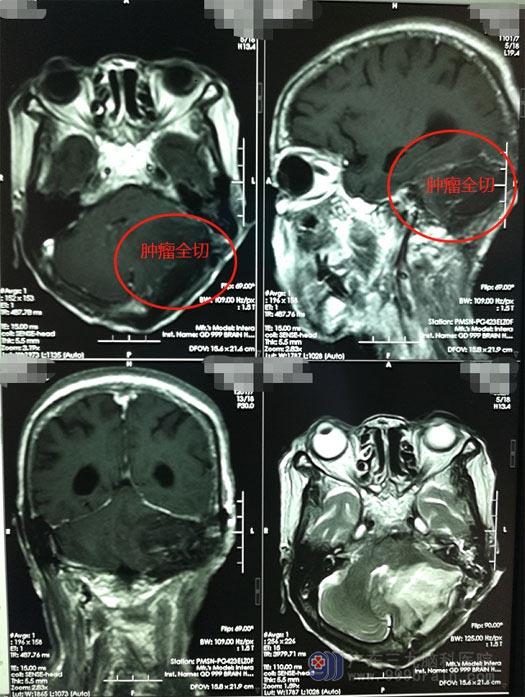

肿瘤体积较大,与横窦关系密切,手术中需要注意保护脑干及后组颅窝神经及重要血管,疏通脑脊液循环;医院副院长、神经外五科主任鲁明带领团队为苏奶奶实施了手术,在高科技显微镜下成功将肿瘤全部摘除。术后苏奶奶可以自主进食饮水,肢体活动良好,未出现术后不良反应。